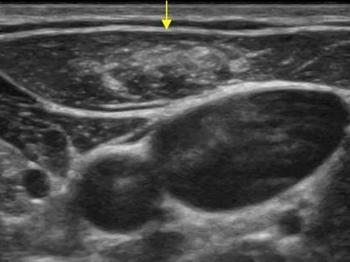

Parotis enfeksiyonlarından en bilineni genellikle çocukluk çağında görülen kabakulaktır. Kabakulak dışında viral ve bakteriyel enfeksiyonlar gelişebilir. Bu durumlarda renkli doppler ultrason tanı açısından önemlidir. Parotisin iyi ve kötü huylu kitleleri mevcuttur. Ultrason incelemesinde parotis kitlesinin şekli, anatomik özellikleri ve doppler inceleme özelliklerine bakılarak tanıya yardımcı olunabilir. Eğer kitle kötü huylu olma potansiyeli taşıyorsa ultrason eşliğinde ince iğne aspirasyon biyopsisi ile patolojik tanı konulabilir. Bir diğer parotis kitlesi sebebi de parotis içinden gelişen lenf nodlarıdır. Genellikle reaktif olan bu lenf nodları (enfeksiyona bağlı) zaman zaman ağrı sebebi olabilir.